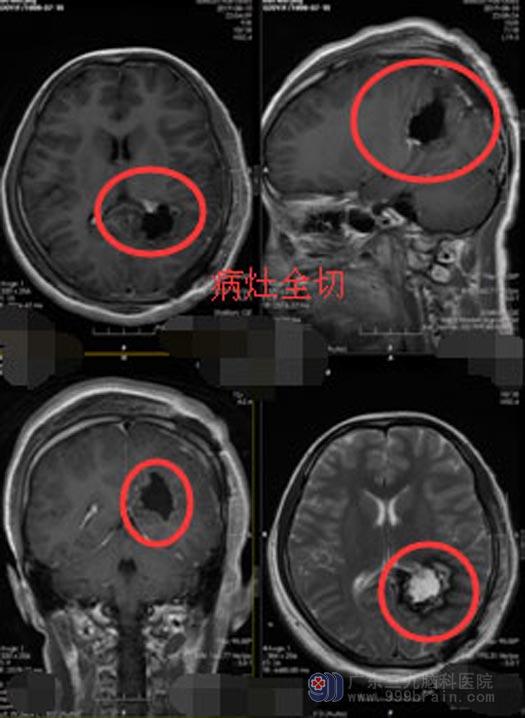

考虑是良性肿瘤可能性大,神经外五科医师团队经过详细讨论,为小静制定了针对性的手术方案,决定实施球囊辅助精准定位,左侧侧脑室后角巨大占位切除术。虽然占位比较大,术中仍可以利用微创技术,显微镜下将肿瘤分块全部切除,周围重要的神经及血管保护完好,手术完成顺利。术后小静恢复良好,无任何不良并发症。

▲手术后